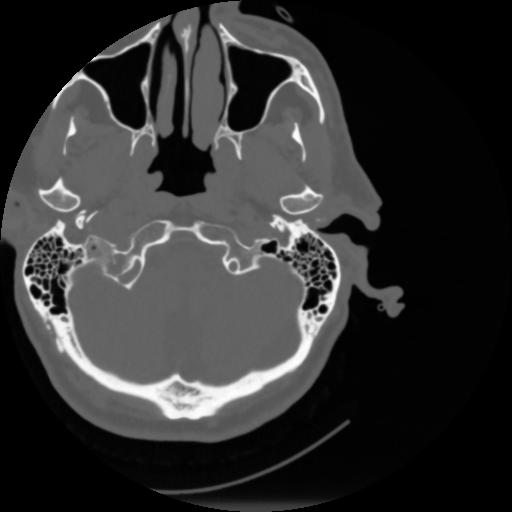

4 CEREBRO,,Vol,0.5,CEREBRO,,